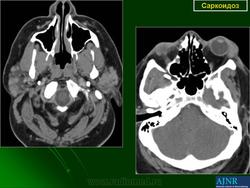

anatpat.unicamp

Саркоидоз твердой мозговой оболочки.

Рисунок 8

Рисунок 8 Нейросаркоидоз.